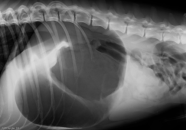

Dort erfolgt die Diagnose durch das klinische Erscheinungsbild und eine Röntgenaufnahme. Nach der Kreislaufstabilisation, der Dekompensation des aufgegasten Magens und der medikamentösen Versorgung müssen die betroffenen Hunde operiert und der Magen wieder in die richtige Position gebracht und dort fixiert werden.

Copyright: https://greyhoundrescue.com.au/news/healthy-hound-corner-bloat/